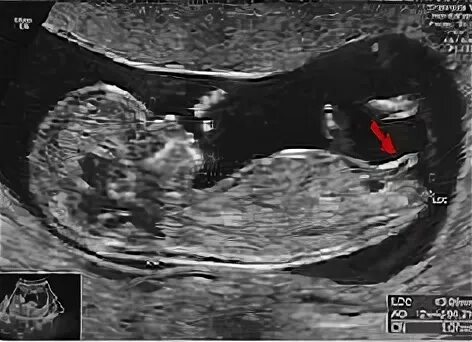

Как определить пол ребенка 12 недель